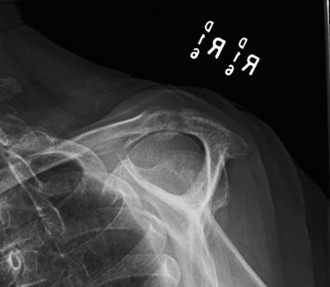

Marked superior migration of the humeral head with severe narrowing of the acromiohumeral interval, measuring approximately 2mm (normal > 7mm). There was evidence of glenohumeral joint space narrowing, particularly superiorly. Significant osteophyte formation was present around the glenoid rim and humeral head. Scalloping and acetabularization of the undersurface of the acromion and coracoacromial arch were visible, a direct consequence of the chronically superiorly migrated humeral head eroding the arch. Subchondral sclerosis and cystic changes were noted on both the humeral head and glenoid.

Interpretation of the provided image

: This X-ray appears to be an AP view of a shoulder demonstrating classic features of severe rotator cuff arthropathy (Hamada Grade 4 or 5). Key findings include: severe superior migration of the humeral head with obliteration of the acromiohumeral interval, marked glenohumeral joint space narrowing, large superior osteophytes on the glenoid, and acetabularization of the acromion. There is also evidence of cystic changes and sclerosis in the humeral head.

Hamada Classification (Radiographic assessment of RCA):

Based on the plain radiographs, the patient's shoulder demonstrated:

Our patient's findings of severe superior migration with an acromiohumeral interval of 2mm, marked acetabularization of the acromion, and significant glenohumeral joint space narrowing with osteophytes and cystic changes, placed him squarely in Hamada Grade 4A (or possibly 4B depending on exact definition of collapse), indicating advanced RCA.